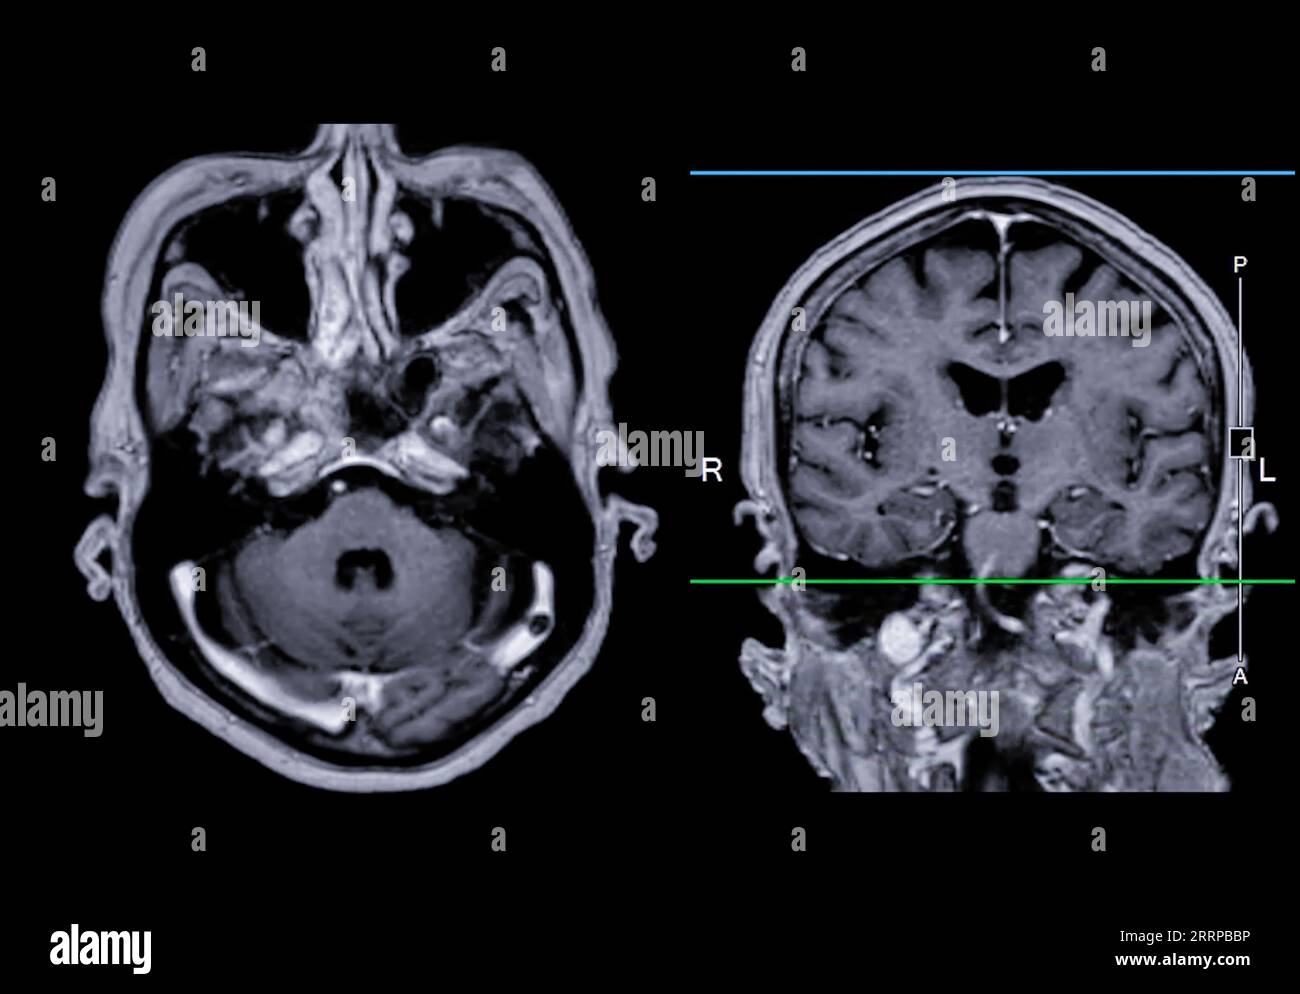

What Can Mri Scans Detect In The Brain. A variant called mr angiography. an mri of the brain can be used to evaluate many symptoms which may be caused by abnormalities in the central nervous system. mra can also be used to detect aneurysms in the brain and vascular malformations — abnormalities of blood vessels in the brain,. doctors use mri scans to diagnose and monitor head injuries and to check for abnormalities in the head or brain. mri can detect abnormalities that might be obscured by bone with other imaging methods. With the mri results in hand,. a head mri is a useful tool for detecting a number of brain conditions, including: using an mri scan, doctors can identify any bleeding or swelling in the brain and determine the extent of any damage. Aneurysms, or bulging in the blood vessels of the brain. mri is used to analyze the anatomy of the brain and to identify some pathological conditions such as cerebrovascular incidents, demyelinating.

A variant called mr angiography. Aneurysms, or bulging in the blood vessels of the brain. With the mri results in hand,. an mri of the brain can be used to evaluate many symptoms which may be caused by abnormalities in the central nervous system. mri can detect abnormalities that might be obscured by bone with other imaging methods. doctors use mri scans to diagnose and monitor head injuries and to check for abnormalities in the head or brain. mri is used to analyze the anatomy of the brain and to identify some pathological conditions such as cerebrovascular incidents, demyelinating. mra can also be used to detect aneurysms in the brain and vascular malformations — abnormalities of blood vessels in the brain,. using an mri scan, doctors can identify any bleeding or swelling in the brain and determine the extent of any damage. a head mri is a useful tool for detecting a number of brain conditions, including:

What Can Mri Scans Detect In The Brain mri is used to analyze the anatomy of the brain and to identify some pathological conditions such as cerebrovascular incidents, demyelinating. mra can also be used to detect aneurysms in the brain and vascular malformations — abnormalities of blood vessels in the brain,. mri is used to analyze the anatomy of the brain and to identify some pathological conditions such as cerebrovascular incidents, demyelinating. A variant called mr angiography. an mri of the brain can be used to evaluate many symptoms which may be caused by abnormalities in the central nervous system. using an mri scan, doctors can identify any bleeding or swelling in the brain and determine the extent of any damage. a head mri is a useful tool for detecting a number of brain conditions, including: With the mri results in hand,. doctors use mri scans to diagnose and monitor head injuries and to check for abnormalities in the head or brain. mri can detect abnormalities that might be obscured by bone with other imaging methods. Aneurysms, or bulging in the blood vessels of the brain.